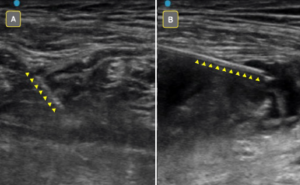

Figure 4A: Poorly visualized needle due to low angle of insonation. Figure 4B: Improved needle visualization after “toeing in” transducer.